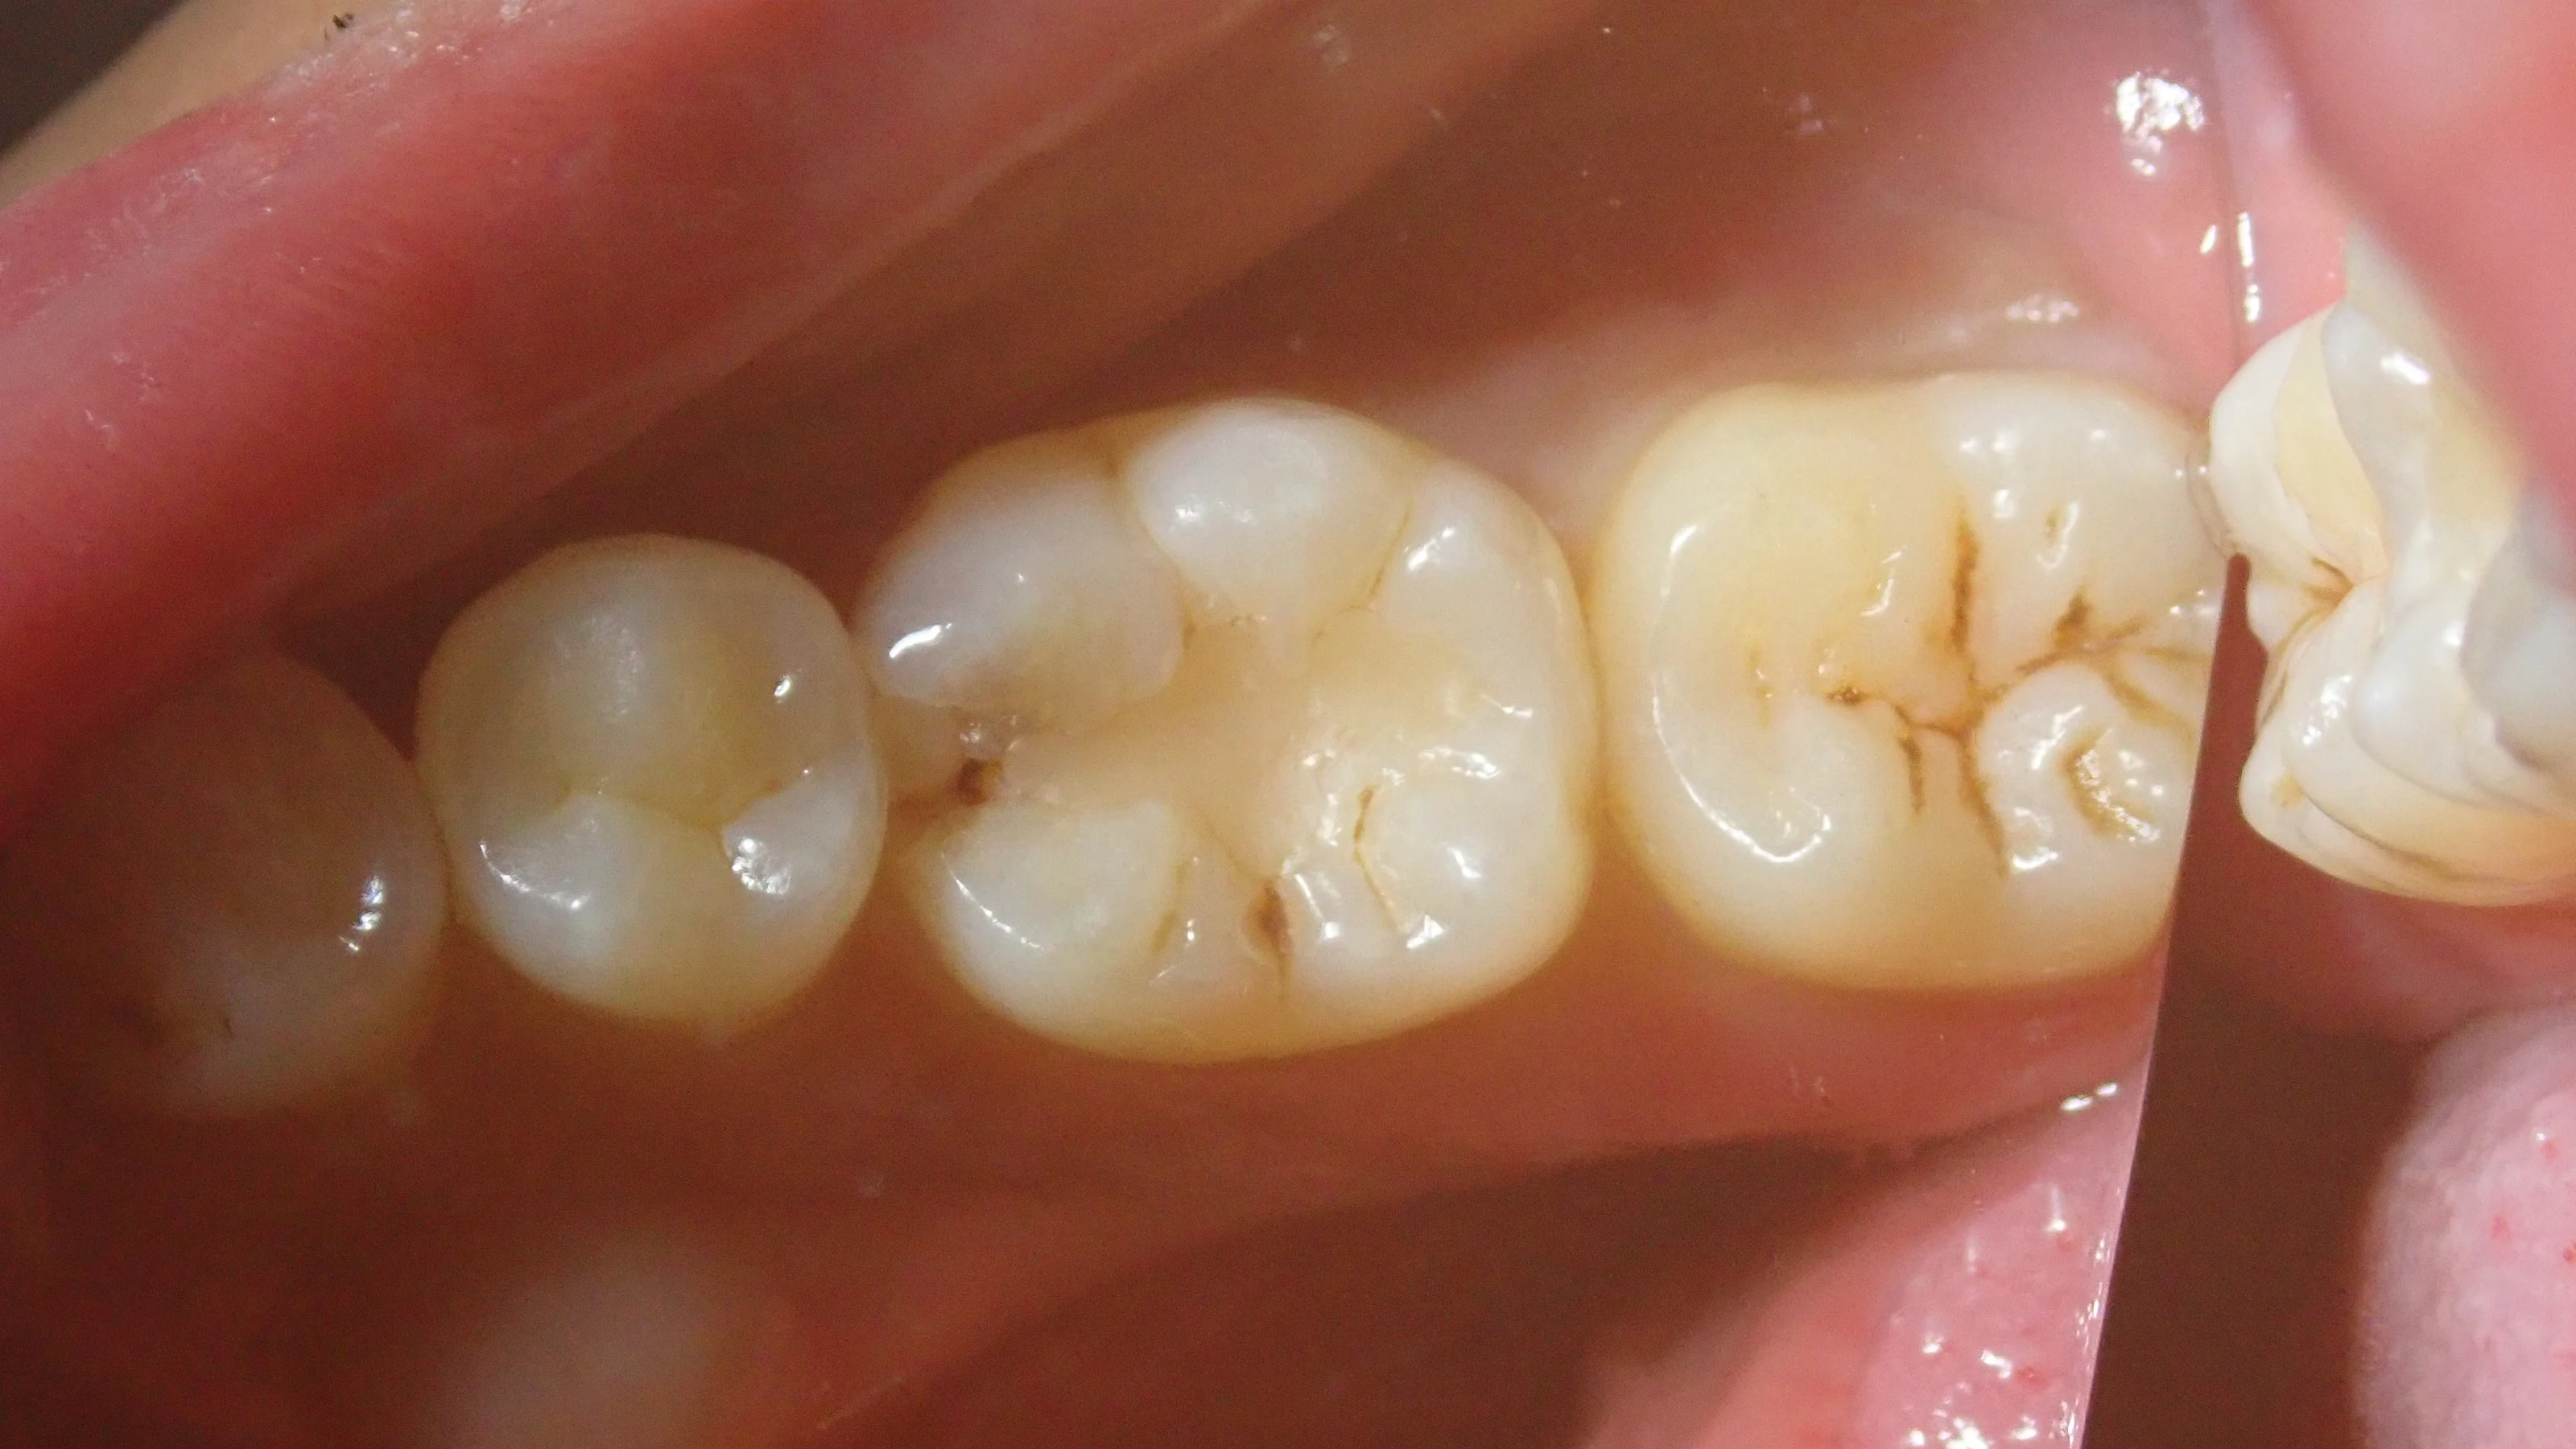

まずは術前の写真です。

どうやら保険適用内のCR(コンポジットレジン)で治療を受けられたようですが、割れてしまい、そこから中に虫歯が侵入してしまったようですね。